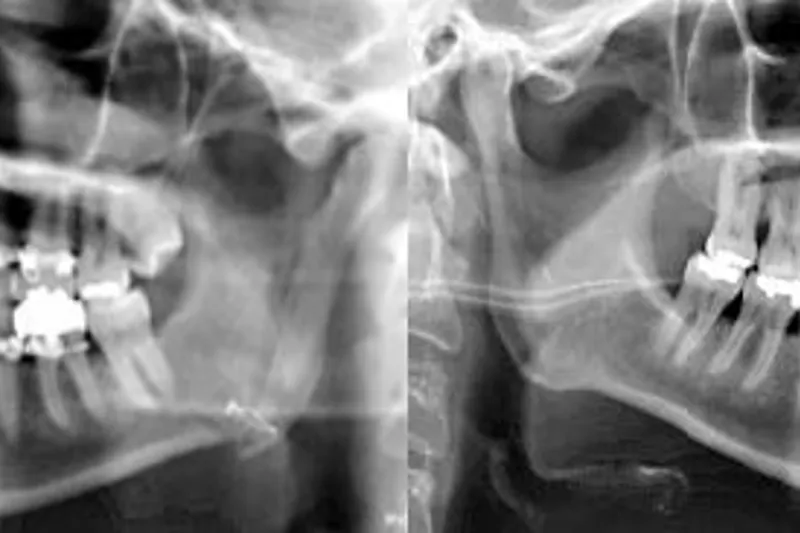

Baggrund – Temporomandibulær dysfunktion er den hyppigste årsag til kroniske orofaciale smerter. Modificeret kondylotomi kan være indiceret ved diskusdysfunktioner i kæbeleddet, hvor konservativ behandling har haft minimal eller ingen effekt. Modificeret kondylotomi blev første gang beskrevet i 1989.

Materiale og metode – I perioden 2000 til 2018 fik 31 patienter foretaget uni- eller bilateral modificeret kondylotomi. Retrospektivt blev gabeevne, smerte, hovedpine og komplikationer evalueret.

Resultater – 29 patienter fik foretaget unilateral modificeret kondylotomi, og to patienter fik foretaget bilateral modificeret kondylotomi på Kæbekirurgisk Afdeling, Aalborg Universitetshospital, Danmark. Alle patienter havde fået stillet diagnosen diskusdysfunktion i kæbeleddet og havde gennemgået konservativ behandling med minimal eller manglende effekt. Den postoperative kontrolperiode var 18,7 15,9 måneder. Smerte ved funktion faldt statistisk signifikant efter behandling med modificeret kondylotomi (P = 0,000). Ydermere blev gabeevnen statistisk signifikant forbedret postoperativt (P = 0,000). Seks patienter udviklede paræstesi af n. buccalis, og en patient fik paræstesi af n. alveolaris inferior. Yderligere komplikationer forekom ikke.